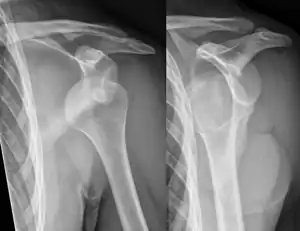

Lightbulb sign indicative of posterior shoulder dislocation shown on the left. On the right, the same shoulder after reduction.

Axillary view of the left shoulder showing a posterior dislocation